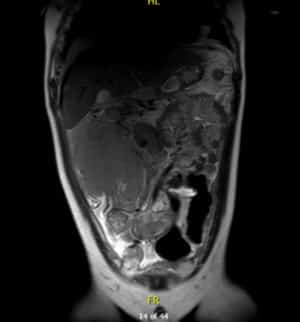

Resonancia magnética

Por su parte, en la resonancia magnética se observa una masa voluminosa infiltrativa en flanco derecho que mide 140 x 120 x150 mm, íntima relación con área ileocecal y colon ascendente al que rodea en su totalidad sin condicionar obstrucción.

Estas pruebas hacían pensar en un linfoma de Burkitt.